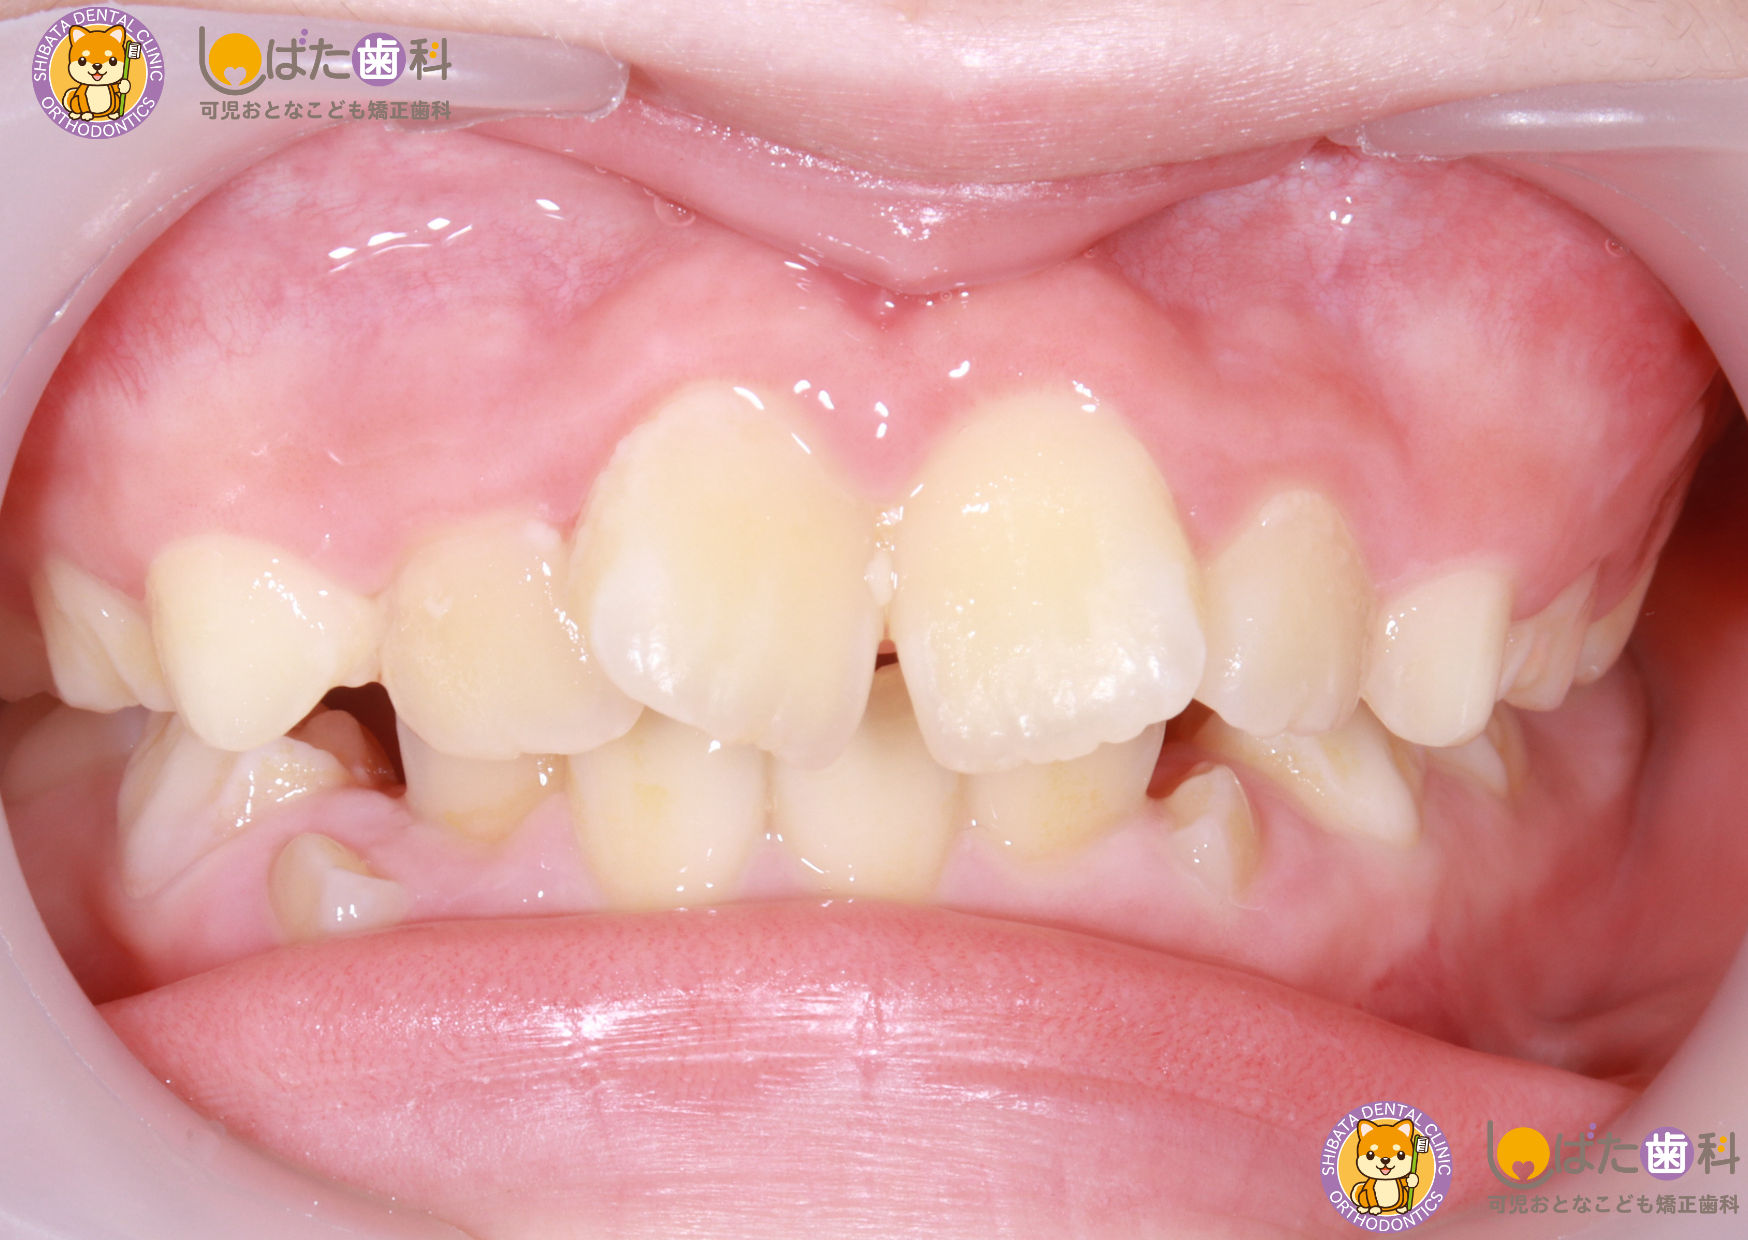

・すきっ歯

乳歯の段階ですきっ歯が見られることは珍しくありませんが、これが成長とともに自然に治る場合もあれば、永久歯が生え揃った後も問題が残ることもあります。